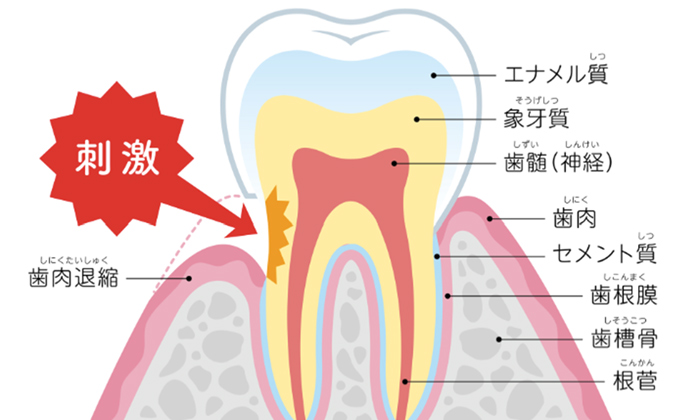

歯の表面のエナメル質の内側と、歯の根には象牙質という組織があります。

この象牙質には象牙細管という無数の小さい管が神経に向かって走っており、ここに刺激が加わると神経に刺激がいくため、しみたり痛みを感じたりします。

TVのCMではこれを知覚ホールと呼んでいますね。力が原因でエナメル質が欠けたり、歯茎が下がって歯の根が露出すると、刺激が伝わりやすくなるため、知覚過敏の症状がでやすくなります。

歯周病や矯正治療などによって歯茎が下がると、歯の根が露出して知覚過敏の症状がでやすくなります。この場合、歯医者で定期的にしみ止めの薬を塗り、歯磨き粉を知覚過敏用に変えることで症状を緩和させることができます。